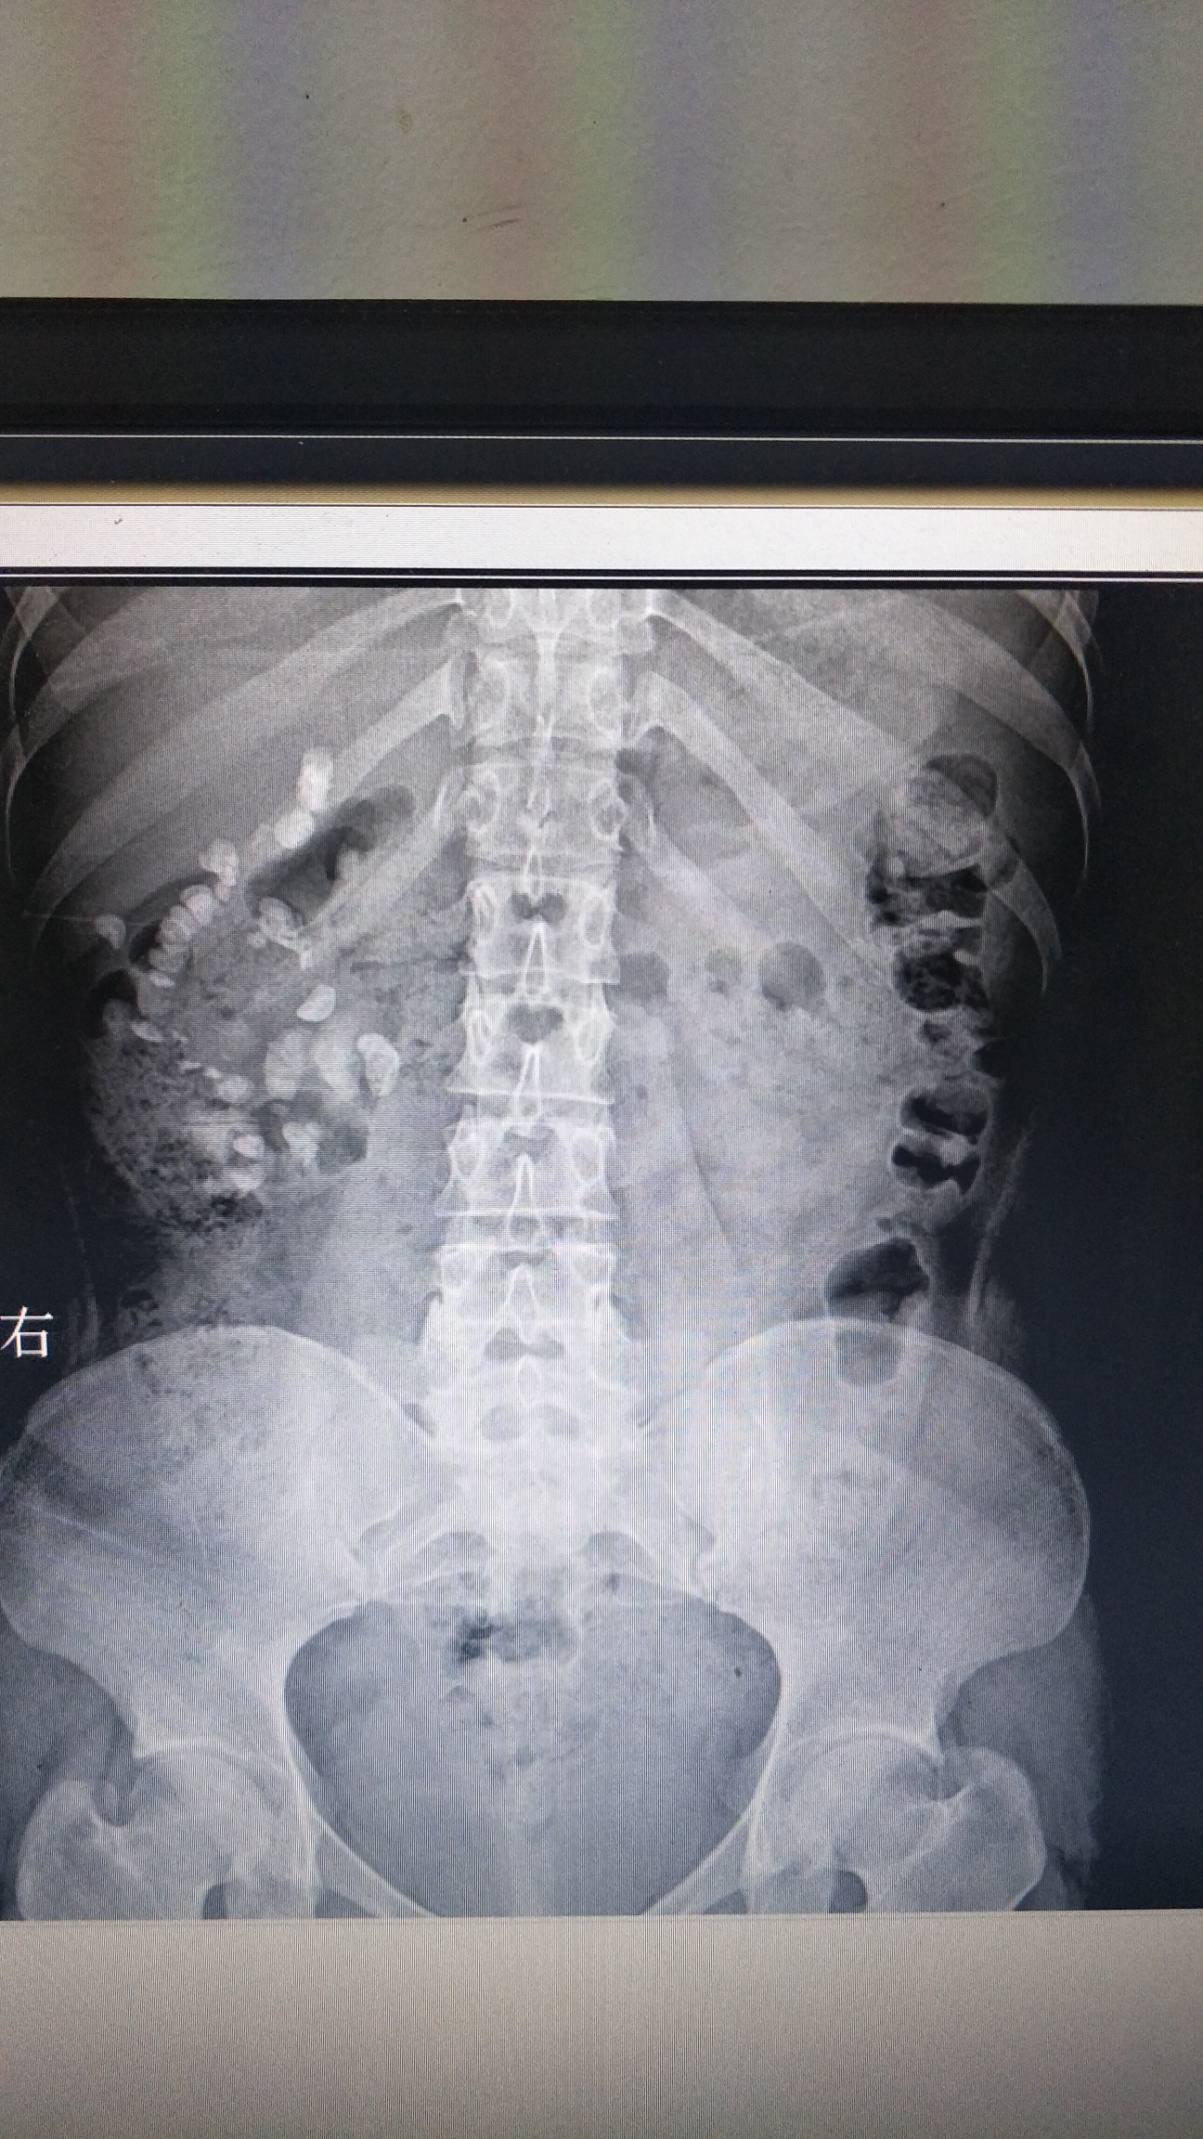

患者:王嬌,女性,21歲。因“體檢發(fā)現(xiàn)右腎結(jié)石8月余”入院,診斷為右腎多發(fā)結(jié)石、右輸尿管結(jié)石、右腎積水。于2019-07-17在全麻下行“輸尿管軟鏡聯(lián)合經(jīng)皮腎鏡右腎結(jié)石碎石取石術(shù)”, 此術(shù)式采取側(cè)仰臥奔跑位,為我科首次采用輸尿管軟鏡聯(lián)合經(jīng)皮腎鏡處理復(fù)雜性腎結(jié)石。優(yōu)點為軟性輸尿管鏡可以觀察和處理經(jīng)皮腎鏡不能達到的腎盂、腎盞內(nèi)的結(jié)石,配合鈥激光碎石效果滿意。對于腎臟復(fù)雜性結(jié)石清除率較高,效果良好,術(shù)后恢復(fù)快,5天后康復(fù)出院,對治療表示滿意。